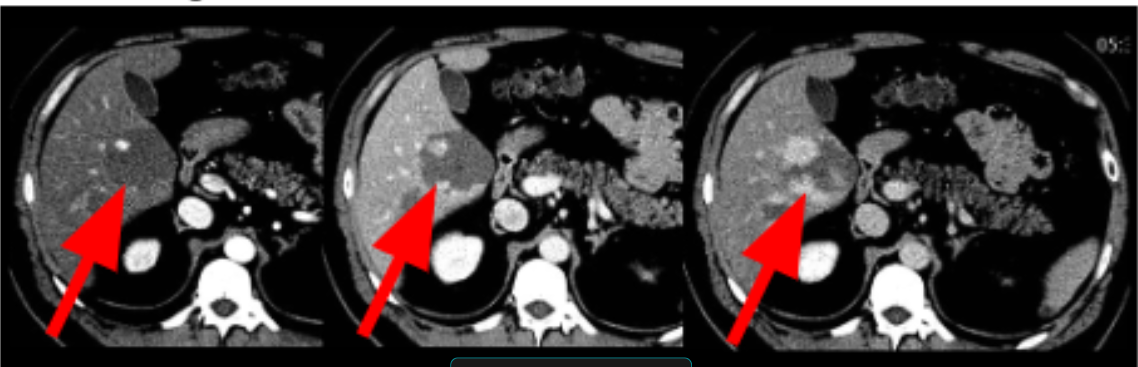

ADENOMA HEPATICO

nsidere a possibilidade de adenoma hepático se estiver diante de uma lesão com hemorragia espontânea, gordura intralesional ou hipervascular sem outro diagnóstico alternativo mais provável.